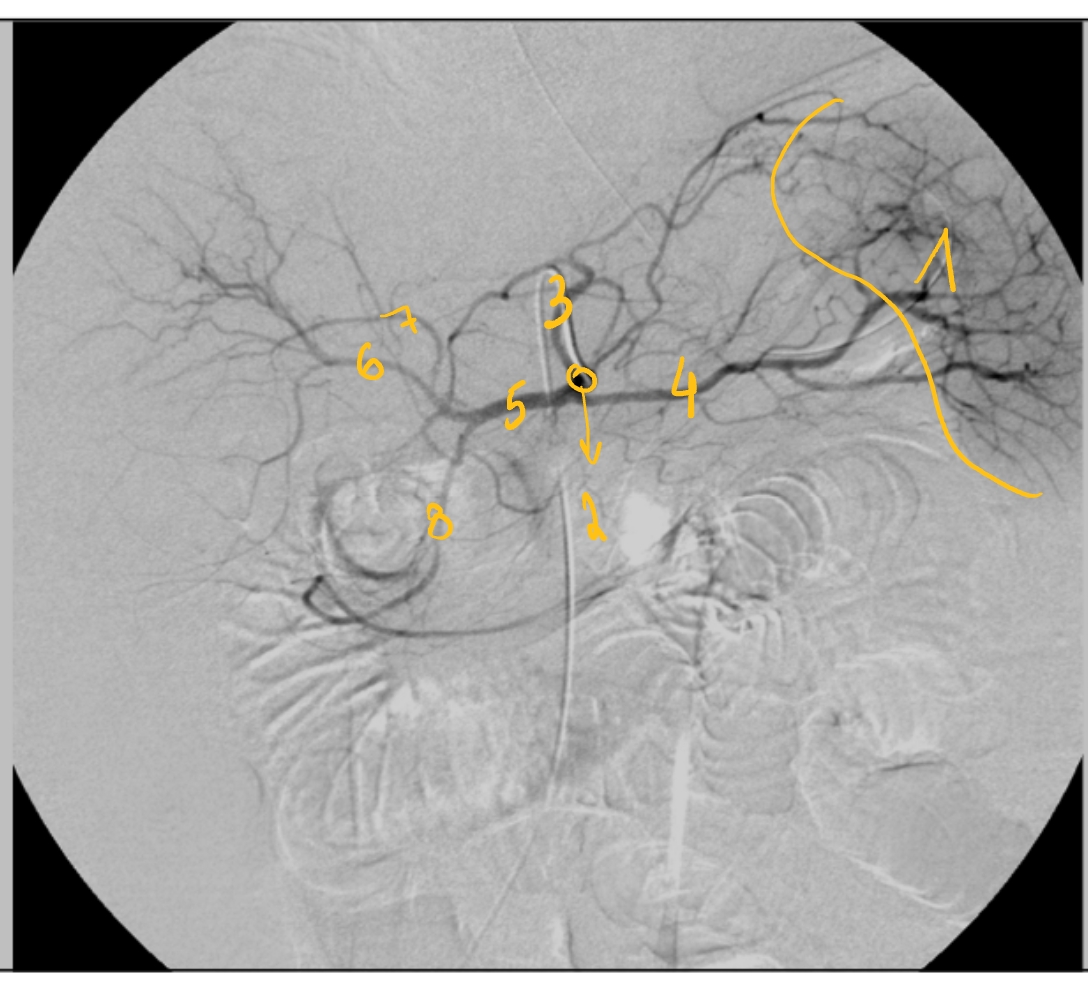

(catheter via a. femoralis → a. iliaca externus → a. iliaca communis → aorta abdominalis → truncus coeliacus)

a. gastroduodenalis

a. hepatica communis

a. gastrica sinistra

a. hepatica sinistra

a. hepatica dextra

a. splenica

milt

truncus coeliacus